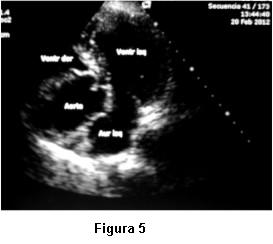

Dada la persistente sospecha clínica de un shunt de derecha a izquierda no detectado por el ETT, se nos solicitó la realización de ETE. Las imágenes transtorácicas pre ETE fueron claras en mostrar una raíz de aorta dilatada, ocupando gran parte de la AD y comprimiendo el anillo tricuspídeo (figura 5). Insuficiencia aórtica moderada. VD colapsado. Flujo a través de válvula tricúspide de difícil detección, no valorable por Doppler. Arteria pulmonar no dilatada. Se realizó inyección de suero agitado y se comprobó masivo pasaje de microburbujas hacia cavidades izquierdas. El ETE mostró adicionalmente un septum interauricular deformado, con un foramen oval persistentemente abierto, hacia el cual se observaba flujo direccionado desde vena cava inferior, lo cual producía un muy severo y constante cortocircuito de derecha a izquierda. Raíz de aorta y aorta ascendente dilatada (44 y 47 mm) con elongación de aórtica torácica. Severa compresión de anillo tricuspídeo por aorta ya descripta (figura 6).